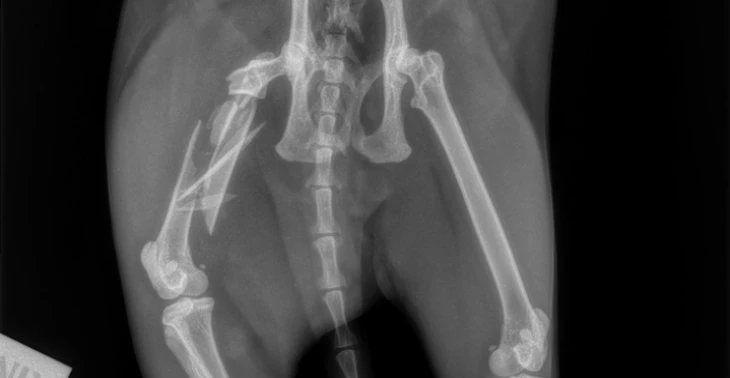

Nu een jaar later hebben ze onze kat noxy haar dijbeen volledig gebroken .De dierenarts en de dieren kliniek bevestigen dat deze spiraalbreuk niet door ongeval is veroorzaakt maar door het moedwillig wringen van het dijbeen .